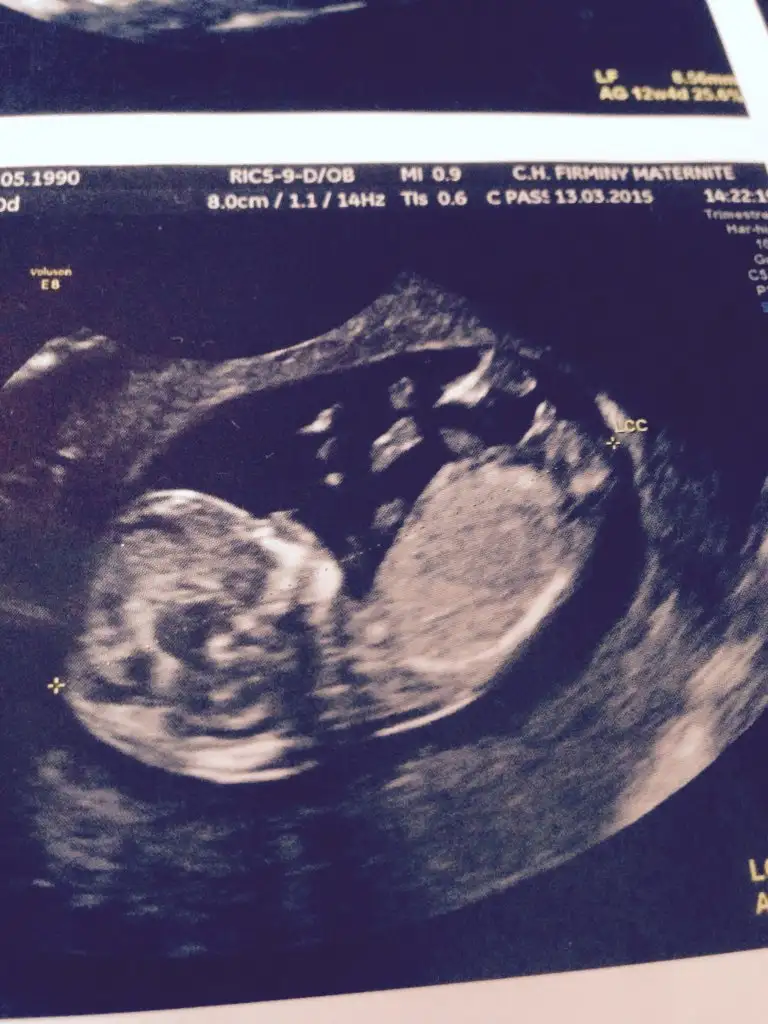

Erkek bence yalniz nub icin erkek annesi 12 . Haftayi bekleKızlar sizce nedirEki Görüntüle 1535231

Dr birşey söylemedimi pekiKizlar 12+4 haftalikmis bebegim bakarmisiniz acaba tahminleriniz nedir ben anlayamadim

yorum yaparmısınız arkadaşlar .iki yeni resim daha yükledim lütfen yorumlarınızı bekliyorum

20 haftalığım bende hala öğrenemeynlerdenim .yorum yaparmısınız arkadaşlar .